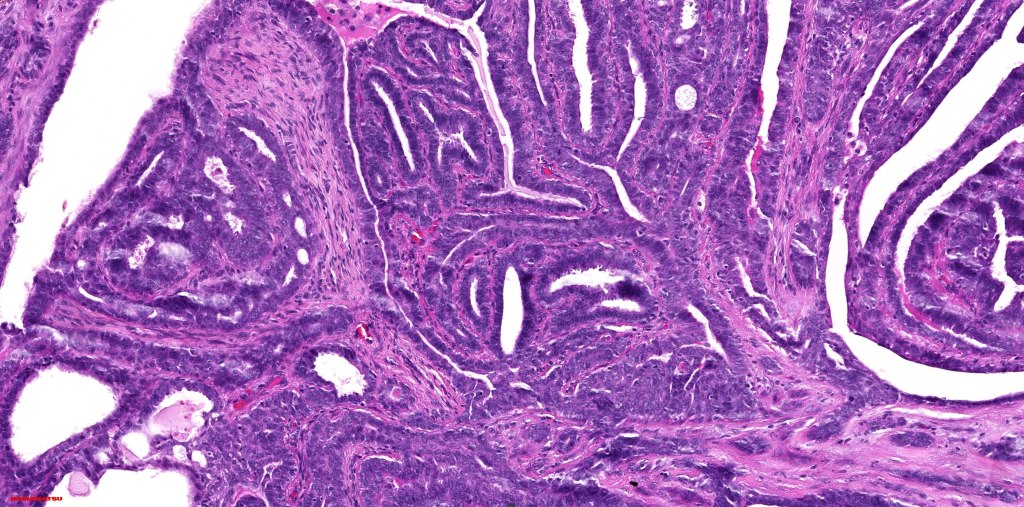

Histological features

•Papillae lined by myoepithelial cells with overlying epithelial cells with eosinophilic cytoplasm showing decapitation secretion

•+/- Oxyphil metaplasia

•Cribriform pattern sometimes evident

•Solid pattern